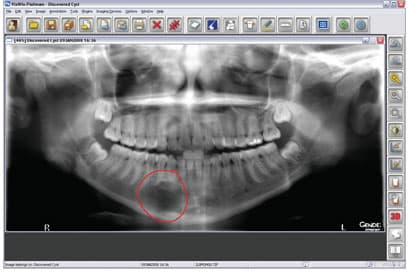

Digital Imaging—Life-Changing Technology

Digital imaging is part of efficient communication, and it adds to the “wow factor.” Patients may see their teeth in the mirror every day, but we must supply images that will let them learn about improving their dentition. For this, digital radiography has become the standard of care in diagnostics. This technology provides superior-quality images in a couple of seconds. It is an excellent diagnostic aid with which to compose a treatment plan. On the screen, we can enhance or zoom in, invert or emboss an image to communicate the possibilities in an unobtrusive way. Sometimes a patient may have a problem such as a fractured restoration that cannot

Digital Imaging – It’s a Win-Win for Everyone!

When patients are educated about the details of their dental health, they are more likely to understand the value of treatment. In my quest to improve my patients' dental experience, about two years ago, I began to explore the various options for digital radiography. At first, I was apprehensive about going digital and how this would affect workflow. After a short training period with my staff, I was happily convinced-digital-imaging advancements improve patient care. One very apparent positive aspect of digital imaging is connected with my imaging software-it both makes my job easier and involves the patients in their own treatment. This easy-to-use imaging software captures and mounts X-rays, offers

Digital Radiography : Don’t Miss Out!

I'm always perplexed by some of hygiene friends who say they don't have digital radiography yet because either the office isn't ready or that their doctors feel it's too expensive. As a hygienist who has seen the light that digital brings to a practice, I see it as my personal mission to help convert these offices. They just don't know what they're missing! When I ask a hygienist what "not ready" means to her and to her office, I hear things like, "We're not looking forward to the 'big' change."..."We don't have computers in the operatories yet."...and "We don't think our patients will take to it." They